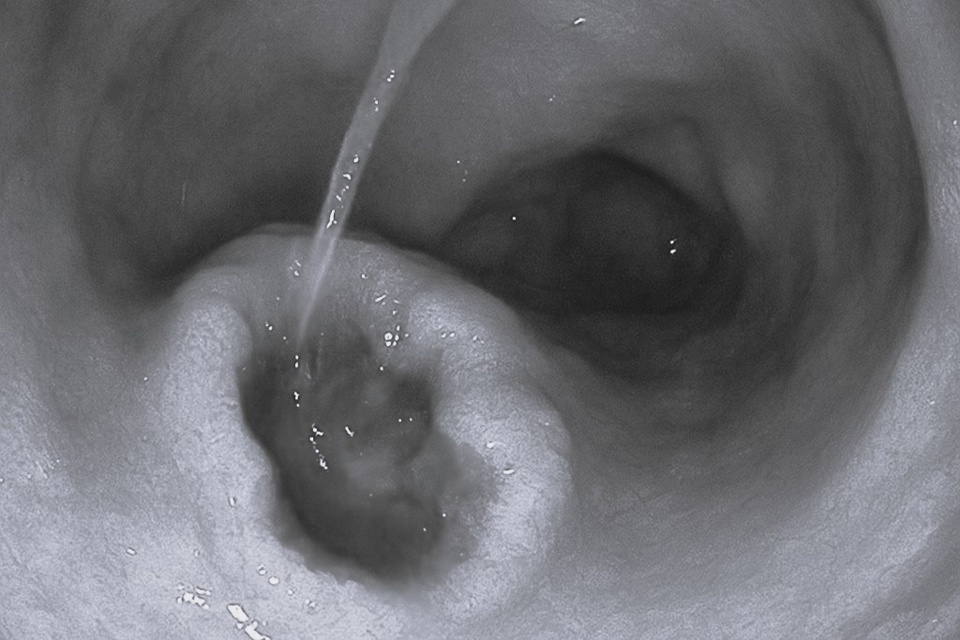

Nhiều người nhập viện trong tình trạng xuất huyết tiêu hóa do lạm dụng thuốc giảm đau. Ảnh: BVCC. |

Các bác sĩ cho biết nhiều trường hợp rơi vào tình trạng rất nặng, điển hình như xuất huyết tiêu hoá do loét dạ dày - tá tràng khiến người bệnh nôn ra máu, đi ngoài phân đen và nhanh chóng trụy mạch nếu không được cấp cứu kịp thời. Một số ca còn tiến triển đến thủng tạng rỗng, phải phẫu thuật cấp cứu.